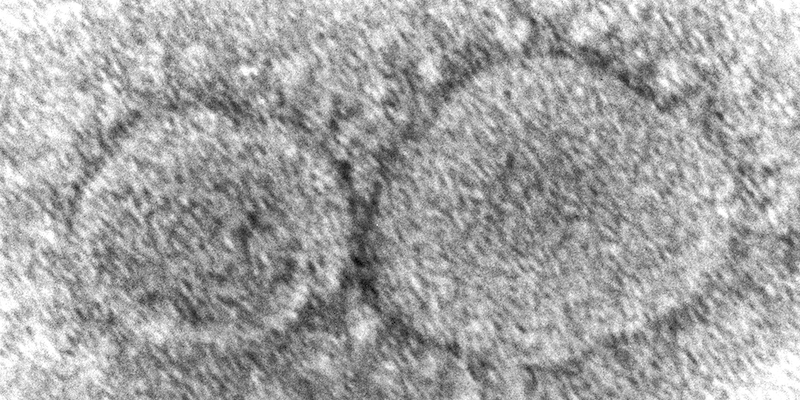

Lunedì il presidente degli Stati Uniti Joe Biden ha firmato una legge che prevede di rendere pubblici quanti più documenti possibili sulle attività di intelligence finora riservate sulle origini del coronavirus. Secondo le agenzie governative statunitensi, questi documenti non contengono elementi che stabiliscano in maniera chiara quale sia l’origine del virus: la decisione di Biden comunque è considerata importante per l’impegno alla trasparenza della sua amministrazione e, come ha detto lo stesso presidente, perché il pubblico possa avere a disposizione «quante più informazioni possibili sull’origine» della pandemia, su cui ormai da tempo sono in corso discussioni.